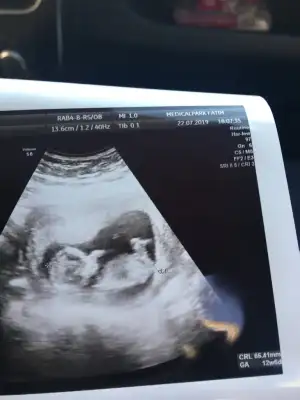

Hanımlar benim bebeğime de yorum yapabilecek biri var mı?? Çok merak ediyorum. Doktor bir tahminde bulundu ama sizler ne söylüceksiniz merak ediyorum :KK54:

Erkek mi dedi doktorunuz

Evet doktorum çok küçük ama erkek gibi, kesin olarak bir sonraki muayenede belli olur dedi :) teşekkür ederim siz erkek mi diyorsunuz ^_^

Bu ultrasonun çekildiği gün söyledi yani tam 12+6 iken tahmin etti, kesin değil sadece erkek gibi dedi.